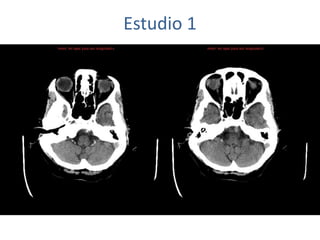

Estudio 1